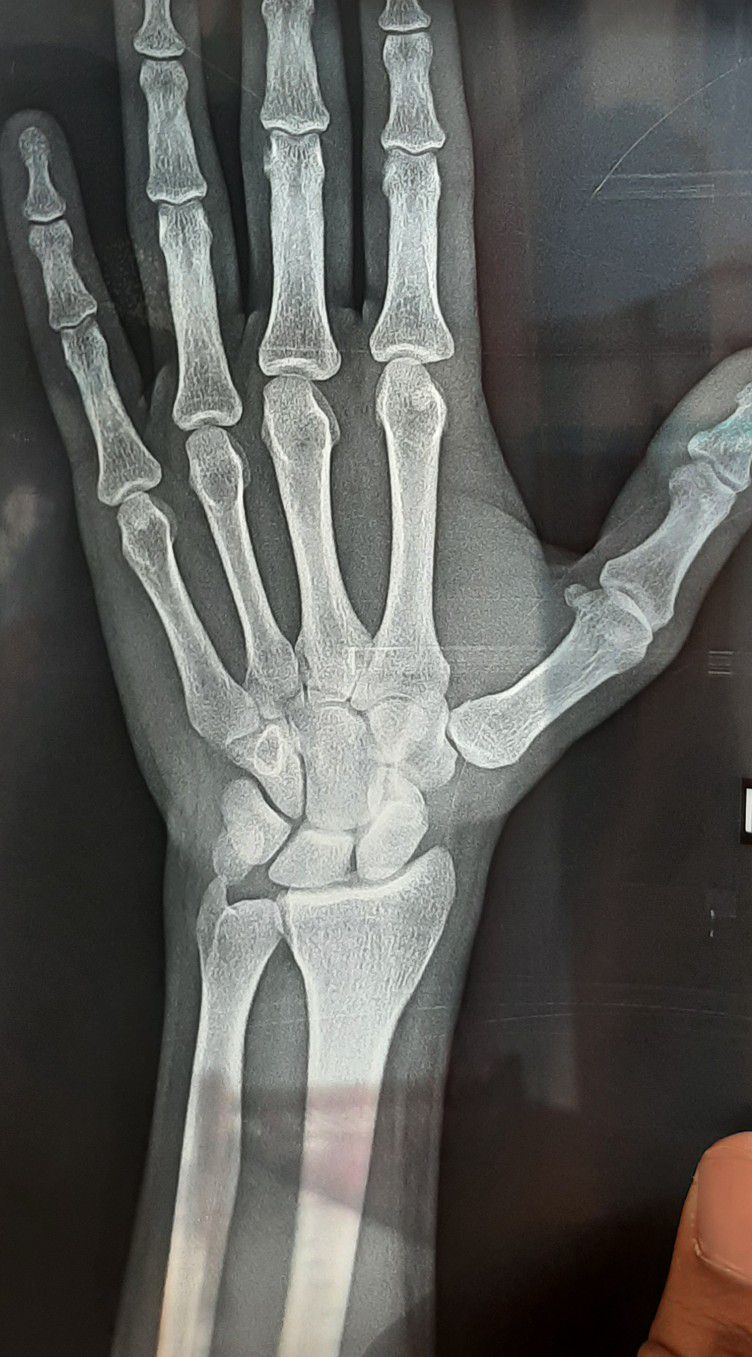

Find fracture

Fracture

Wrist

Find